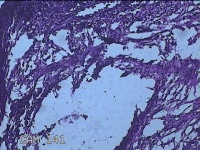

左侧小指背侧结节

性别

女

年龄

44岁

临床诊断

皮下囊肿

一般病史

发现左侧小指背侧结节8年余,无明显疼痛及不适。

标本名称

大体所见

灰白粉红色结节1.8x1.3x0.3cm一个,表面光滑,切开结节呈实性,切面灰白粉红色,质软。